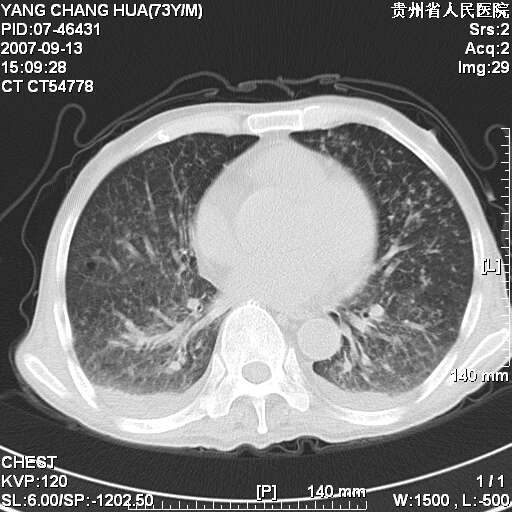

图像没有传全。肺部为感染性病灶;肺囊肿;双侧胸腔积液;肝脾肿大;腹水。

双肺部为感染性病灶.双侧胸腔积液;肝脾肿大;腹水.

双肺部为感染性病灶.双侧胸腔积液;肝脾肿大;脾脏密度不均,不除外脾侵润?腹水.

双肺部为感染性病灶.双侧胸腔积液;肝脾肿大;腹水

图片不全.就这几张图片.无法诊断淋巴瘤的,我考虑:双肺部为炎性病灶.双侧胸腔积液;肝脾肿大;腹水

双肺点片状影,以双上肺改变明显.双侧胸腔积液.为感染性病灶,但不除外结核.

双上肺继发型肺结核。

双侧胸腔积液。

肺大泡。

双肺散在斑片状及多发小结节状阴影,边缘模糊,双上肺野明显,双侧胸膜腔少量积液,纵隔及肺门区未见明显肿大淋巴结,肝脾肿大,脾内见多发低密度区,结合临床考虑恶性淋巴瘤(肺内表现为肺炎肺泡型),单看影像表现,肺结核不能排除。建议结合实验室检查或表浅淋巴结活检。

肺部为;恶性淋巴瘤;双侧胸腔积液;肝脾肿大;腹水。